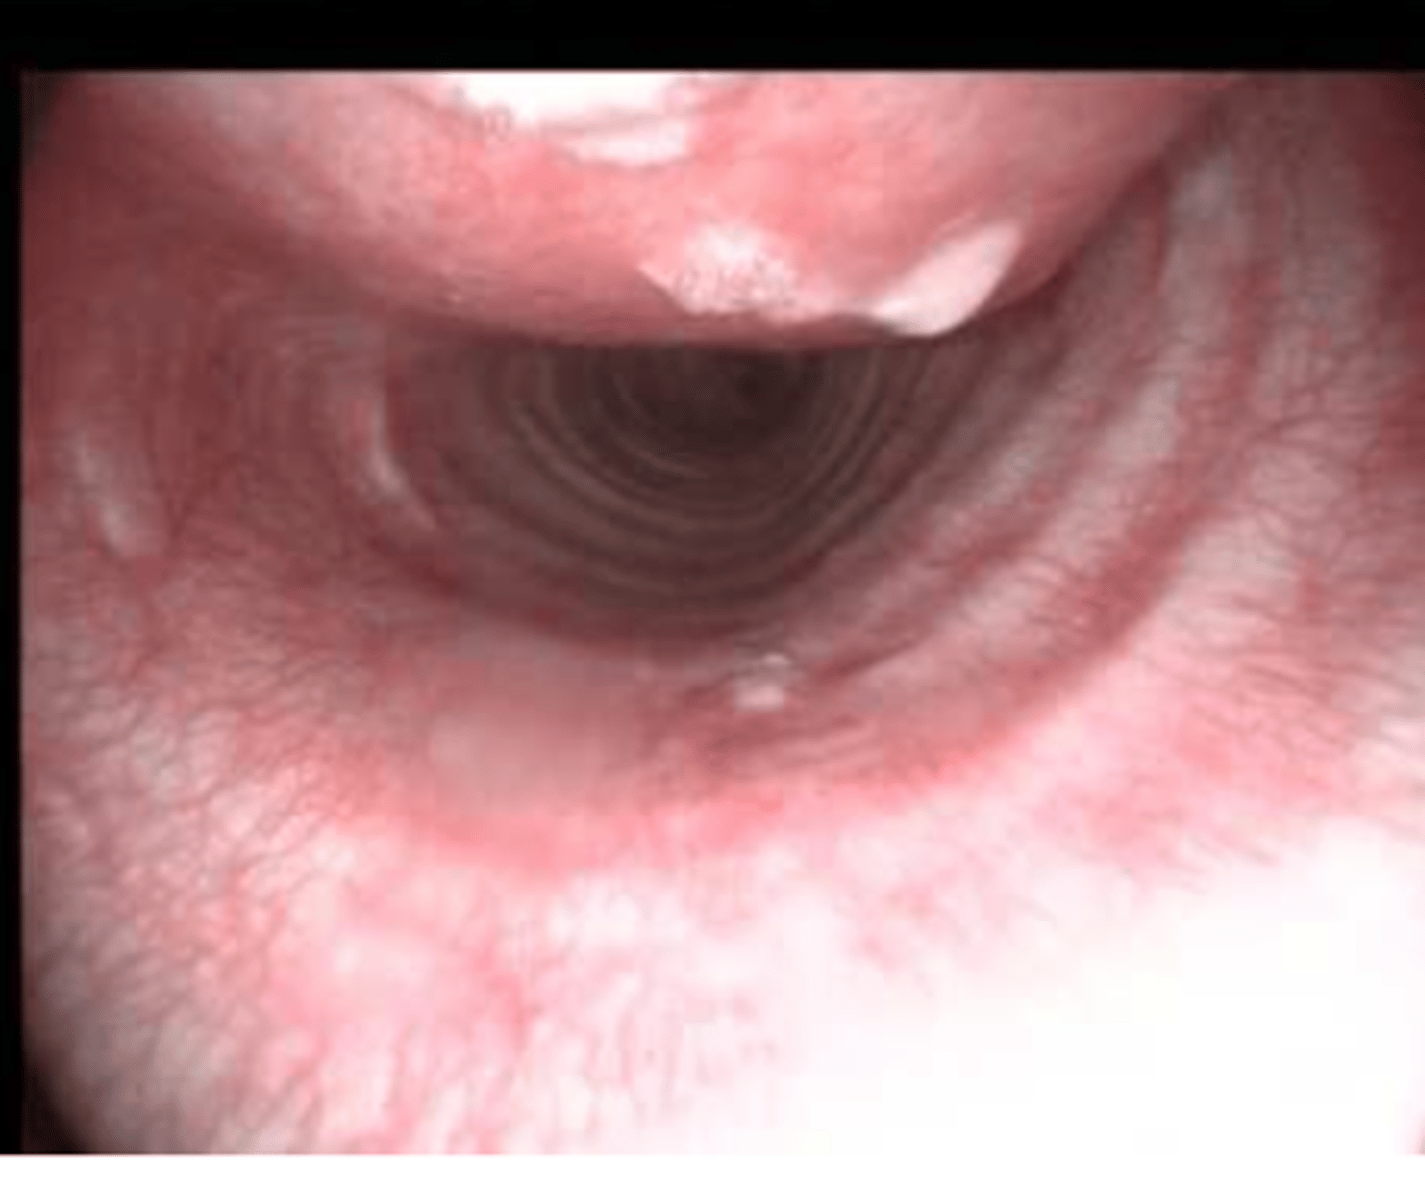

internal inspection of the larynx

what is a laryngoscope used for?

a laryngoscope

what is this?